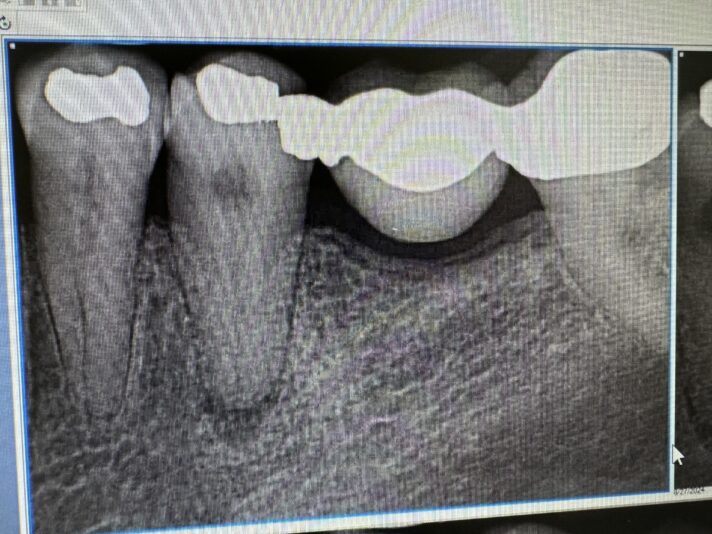

Dr. started the discussion #10 implant site in the forum Implant Tx Planning a year ago

#10 is planned for a 3.2x10mm implant. The socket was grafted about 4 months prior to the CBCT. I skewed it more towards the palate to ensure the 1.5mm buccal bone (which I believe is more important to have that thickness on buccal rather than the palate). I do have 2+mm buccal bone in the incisal 4mm of the implant. My concern still is…